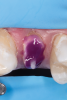

Fig 3. After endodontic treatment, crown lengthening was performed to develop an ideal ferrule effect.

Figure 3

Fig 4. An adequate collar effect of 2 mm of sound tooth structure would provide an anti-rotational feature for the stability of the crown.

Figure 4

Fig 5. Buccal view of optimal ferrule effect with a healthy biological framework.

Figure 5